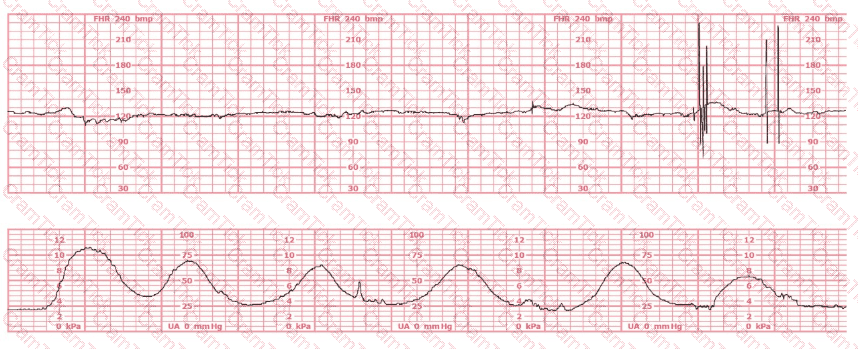

A woman at 41-weeks gestation is being induced. She is 2 cm dilated and is on oxytocin at 8 milliunits/minute. Based on the fetal heart rate tracing shown, the best initial response is to: